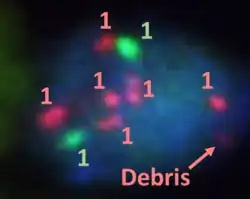

Fluorescence in situ hybridisation

FISH can be used to measure the number of copies of the gene which are present and is thought to be more reliable than immunohistochemistry.[47] It usually uses chromosome enumeration probe 17 (CEP17) to count the amount of chromosomes. Hence, the HER2/CEP17 ratio reflects any amplification of HER2 as compared to the number of chromosomes. The signals of 20 cells are usually counted.

-

This cell displays 2 signals of HER2 (red) and 3 signals of CEP17 (green)

This cell displays 2 signals of HER2 (red) and 3 signals of CEP17 (green) -

Two signals that are closer to each other than the signal diameter count as one.

Two signals that are closer to each other than the signal diameter count as one. -

One of these signals is too faint, and is presumably debris.

One of these signals is too faint, and is presumably debris. -

Cells with only one type of signal are excluded from the count.

Cells with only one type of signal are excluded from the count. -

Overlapping cells are also excluded from the count.

Overlapping cells are also excluded from the count. -

A yellow signal counts as one red and one green (which are overlapping)

A yellow signal counts as one red and one green (which are overlapping)